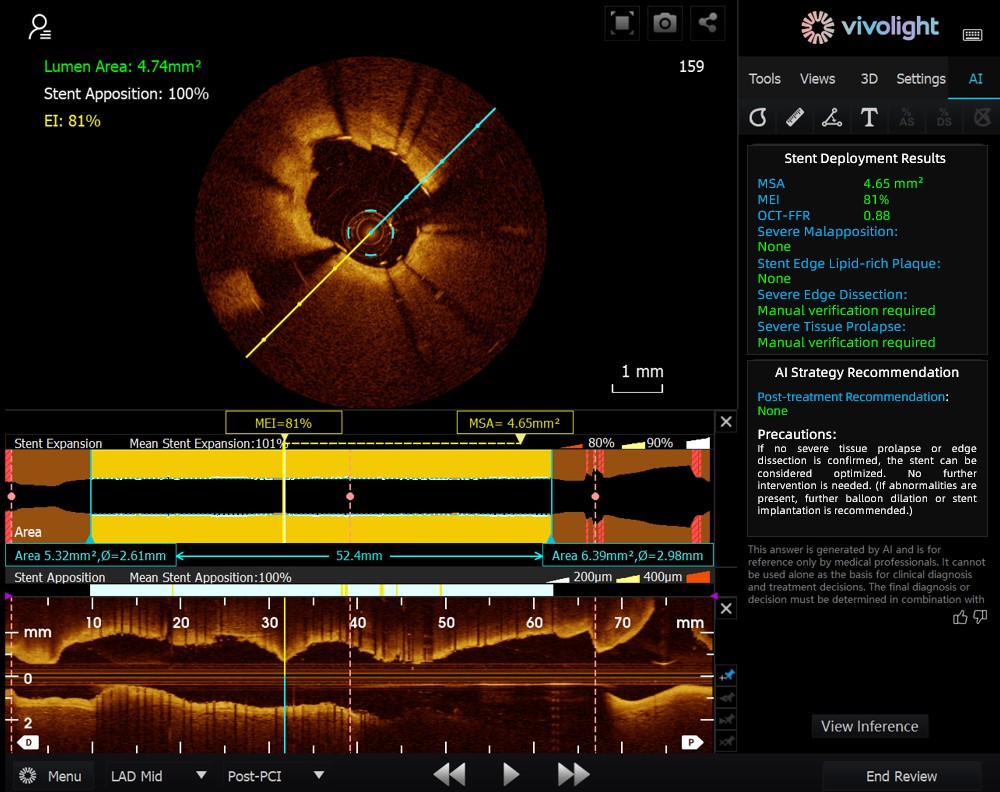

Developed based on Vivolight Medical’s OCT system, the AI-OCT is a next-generation intelligent decision-support system for intravascular imaging. It integrates scattered intravascular imaging diagnostic data—including lumen diameter, culprit lesions, OCT-FFR, and plaque natures—into comprehensive treatment strategies and actionable recommendations. As an independent research software embedded in the OCT platform, it is co-developed with various hospitals to create customized versions tailored to specific clinical needs.

During the cutting-edge forum, experts emphasized that AI-OCT System represents a transformative shift from "viewing images" to "delivering treatment plans"—addressing the challenges of information overload and complex decision-making in cardiac interventional procedures, which traditionally rely heavily on physician experience. Key advantages of the system include:

● Real-time Intraoperative Guidance: It dynamically organizes diagnostic information during surgery, providing key metrics and clinical recommendations.

● Evidence-based Decision-Making: All suggestions align with expert consensus and clinical guidelines, ensuring rigor and reliability.

The AI-OCT System adopts a "small model + big data + large model" architecture: small models enable precise image interpretation, while large models drive comprehensive clinical reasoning. Leveraging high-quality cardiovascular databases and Retrieval-Augmented Generation (RAG) technology, it delivers end-to-end support from lesion assessment to treatment strategy development.